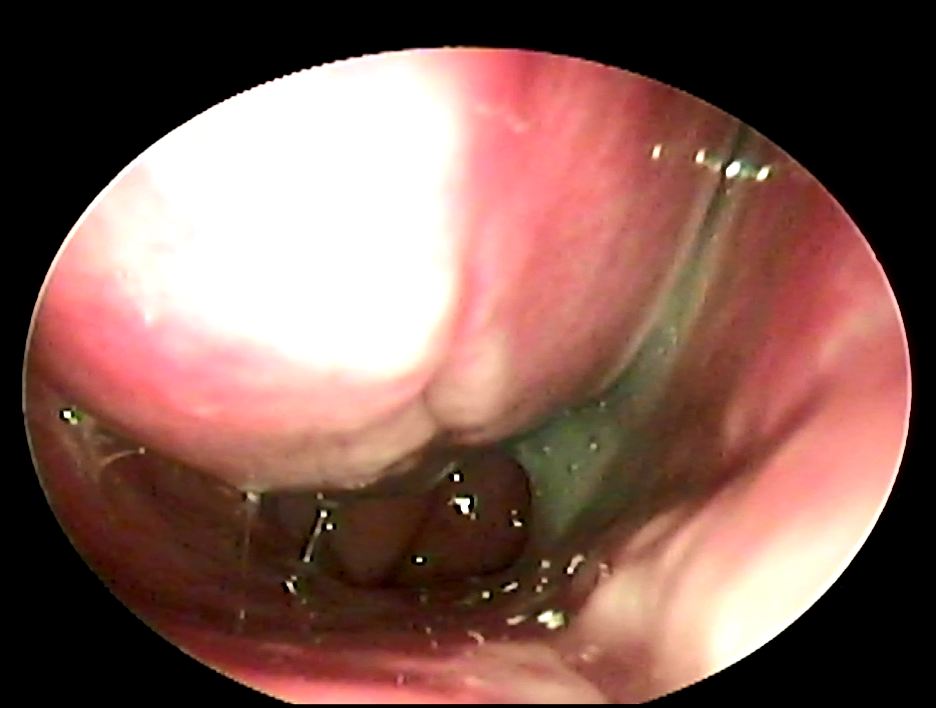

鼻竇是我們顱骨內的空腔,一般人通常會具有上頷竇、前篩竇、後篩竇、蝶竇、額竇等等,他們都跟我們的鼻腔有相通,所以通常鼻竇發炎的時候裡面的分泌物會跑到鼻腔中,導致病人會有膿鼻涕或是鼻涕倒流的症狀,一般來說鼻竇炎可以分為急性、亞急性或慢性,根據不同的感染原又可以分為細菌、病毒或是黴菌,其中最常見的是病毒性感染,每年在美國大約有3100人有得過鼻竇炎,是排名前五大可能會用到抗生素的疾病,當感染的時候鼻竇黏膜會腫脹導致鼻竇開口堵塞,同時病毒或細菌也會影響纖毛運動導致黏液排出困難進而堆積,所以就形成了更容易讓細菌或是病毒滋長的環境,一般來說超過10天以上都沒有任何進步的會高度懷疑是細菌性感染,或是一開始有進步又變嚴重了也會懷疑是細菌性感染,病毒感染通常是症狀治療,細菌性感染一般會給予抗生素,有時也會建議鼻內類固醇的使用以及鼻腔沖洗;一般鼻竇炎的診斷是依據病史以及理學檢查或室內視鏡檢查,不會常規使用影像學檢查除非是懷疑有併發症或是預計要手術治療的時候才會使用,影像學檢查無法判斷是細菌或是病毒性來源,至於細菌培養比較常用於懷疑有抗藥性的病人或是免疫不全的病人身上。

通常單側的鼻竇炎要最為小心,可能是腫瘤、黴菌感染或是牙科處置不當從口腔跑來的細菌,這時候藥物的治療反應就會不好,有時候甚至需要手術治療,鼻竇炎如果延遲治療有時候甚至會引起眼球或眼球旁膿瘍、腦部海綿竇栓塞、腦部膿瘍等等嚴重的併發症,所以如果一直有膿鼻涕沒有改善,請一定要給耳鼻喉專科醫師詳細檢查喔!!